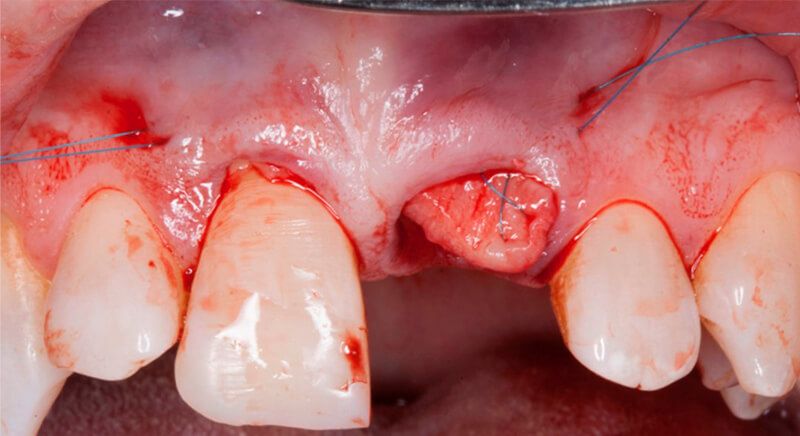

Once tooth 2.1 had been extracted, it was decided that it was not advisable to place an implant immediately as the bone conditions were not ideal and the gum did not have sufficient thickness. We opted for a treatment to preserve the socket and to delay implant insertion.

The socket was filled with a xenograft after the extraction and a graft of connective tissue was placed in the vestibular area of the two upper central incisors.

The tissue with epithelium was taken from the palate and de-epithelialized outside of the mouth. This obtains a lamina propria graft with better density and quality than if it were obtained with a single incision to the palate.